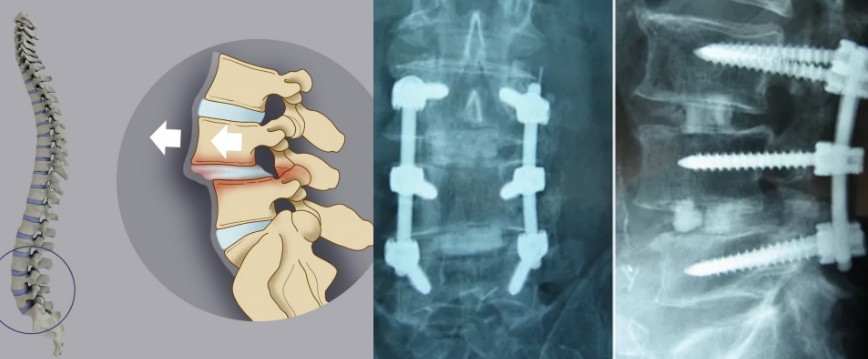

- спондилолистез (смещение позвонков относительно друг друга).

Система фиксации состоит из стержней, размещенных вдоль позвоночника, и винтов, имплантируемых в тело позвонков. Винты выбираются максимальной длины и диаметра для надежного крепления, но их размеры рассчитываются так, чтобы избежать повреждения сосудов и нервов.

При операции в области физиологического лордоза, например, в поясничном отделе, фиксатор устанавливается в естественном положении. Системы транспедикулярной фиксации (ТПФ) разрабатываются с учетом адаптации к изгибам позвоночника во время установки.

Современные конструкции позволяют устанавливать фиксаторы под кожей без разрезов, используя перкутанный метод. Существуют различные способы контроля точности установки винтов, включая механические и ультразвуковые щупы, навигационные системы и другие технологии. Часто применяется цементирование: в тело позвонков вводится специальный костный цемент, который укрепляет винты. Эта процедура особенно важна при остеопорозе.